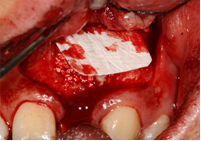

Trong những trường hợp khuyết hỏng xương ổ răng lớn, cần phải ghép xương để cấy ghép implant thì xương khối tự thân là lựa chọn hàng đầu vì có những ưu điểm như tính ổn định cơ học cao chống lại áp lực của mô mềm, ít tiêu,...Vị trí cho xương khối có thể là mào chậu, cằm, xương hàm dưới. Thể tích xương được lấy tùy vào thể tích khuyết hổng cần phục hồi.

LẤY XƯƠNG CẰM GHÉP VÀO VỊ TRÍ KHUYẾT HỔNG

Ghép xương cằm và xương hạt

Dùng màng tự tiêu

Khâu đóng kín vết thương